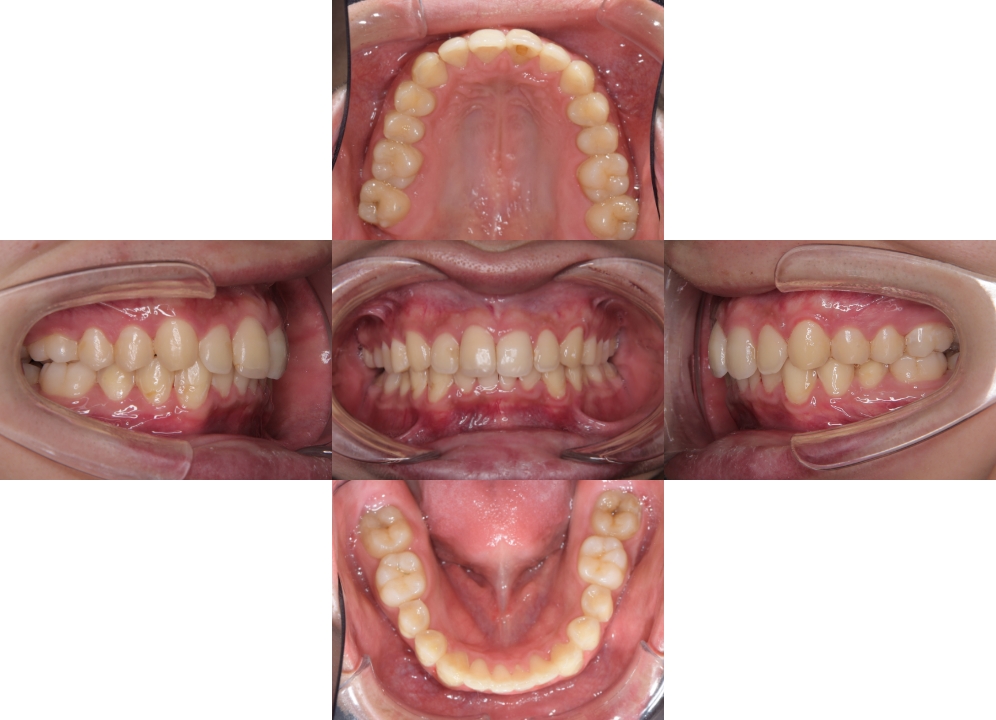

症例03

| 主訴 | 歯並びがガタガタしている。 |

| 診断名あるいは主な症状 | 過蓋咬合、叢生 |

| 年齢/性別 | 26歳・女性 |

| 矯正ステージ | 大人の矯正治療 |

| 治療方法 |

ワイヤー矯正 歯科矯正用アンカースクリュー(3本) |

| 抜歯部位/抜歯有無 | 抜歯 |

| 治療内容 | 上下顎の奥歯を後方に移動後、ガタガタの改善と上下顎前歯を後退させた。 |

| 費用 |

90万円程度(2025.10時点の料金となります。) ※矯正基本料金、アンカースクリュー、審美ブラケットを含む |

| 治療期間 | 2年8ヶ月 |

| 主なリスク・副作用 | 痛み、歯根吸収、歯肉退縮、虫歯、後戻り |